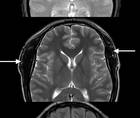

Two recent, large, phase three multicenter studies, the PREEMPT 1 and 2 trials, have shown that BoNTA is an effective treatment for adults withCM.21,22 These studies enrolled 1,384 subjects with CM in trials consisting of a 24-week, double-blind, parallel-group, placebo-controlled phase followed by a 32-week open-label phase. All subjects received at least a minimum dose of 155 units o fBoNTA administered at 31 injection sites across seven head and neck muscles using a fixed-site, fixed-dose injection paradigm and up to extra 40 units into the temporalis, occipitalis, and/or trapeziususing a modified follow-the-pain approach. (Table 2) The clinician performing the injections selected additional sites for injection based on pain location, muscle tenderness, and their personal judgment. Subjects receiving BoNTA in the doubleblindphase had statistically significant improvement from baseline after injection compared with placebo treatment in multiple clinical domains, including mean frequency of headache days and headache episodes. BoNTA-treated subjects also had fewer migraine episodes, fewer moderate or severe headache days than the placebo group. BoNTA subjects took similar amounts of acute medication but fewer triptans than controls. BoNTA treatment also significantly improved measures of disability and health-related quality of life. Based on the results of these two large randomized placebo-controls trials, the US Food and Drug Administration recently approved BoNTA for the treatment of CM.